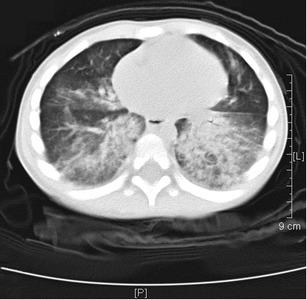

The study group consisted of 23 boys (69.7 %) and 10 girls (30.3 %), with ages ranging from 4 mo to 4 y. They were admitted to the hospital 2 h to 13 d after ingesting the oil-based substance. By the time of admission, most patients presented with respiratory distress and other symptoms, including tachypnea (n = 21), cough (n = 25), mild fever (n = 18), progressive dyspnea (n = 12), and pneumorrhagia (n = 5); six patients received mechanical ventilation because of complicated respiratory distress syndrome. The most common laboratory observations were leukocytosis (25 of 33, 75.8 %), neutrophilia (23 of 33, 69.7 %), and anemia (8 of 33, 24.2 %). Serum biochemical examination showed elevated sedimentation rates (24 of 33, 72.7 %), lactate dehydrogenase levels (18 of 33, 54.5 %), and C-reactive protein levels (17 of 33, 51.5 %). The most common finding on computed tomography (CT) scans was areas of consolidation. Within the follow-up duration of 2 wk to 6 mo, all patients with clinical symptoms of ELP experienced remission, and none died. The CT scans of most of the cases were normal by 1 to 3 mo, except for two patients who showed complete improvement 6 mo after treatment.

研究组包括23例男孩(69.7%)和10例女孩(30.3%),年龄范围为4个月至4岁。他们在摄入油性物质后2小时至13天入院。入院时,大多数患者表现为呼吸窘迫及其他症状,包括呼吸急促(n = 21)、咳嗽(n = 25)、低热(n = 18)、进行性呼吸困难(n = 12)及肺出血(n = 5);6例患者因并发呼吸窘迫综合征接受机械通气。最常见的实验室检查结果为白细胞增多(33例中的25例,75.8%)、中性粒细胞增多(33例中的23例,69.7%)及贫血(33例中的8例,24.2%)。血清生化检查显示血沉升高(33例中的24例,72.7%)、乳酸脱氢酶水平升高(33例中的18例,54.5%)及C反应蛋白水平升高(33例中的17例,51.5%)。计算机断层扫描(CT)最常见的表现为实变区。在2周至6个月的随访期内,所有有ELP临床症状的患者症状均缓解,无死亡病例。大多数病例在1至3个月时CT扫描结果正常,2例患者在治疗6个月后完全恢复。